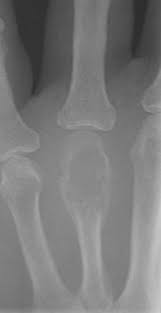

People can die from bone cancer but it all depends on the type of bone cancer, where is it located, age, and treatment. Bone cancer staging system is called the tnm system, based on 4 factors: However, chemotherapy is not currently used to treat chondrosarcoma (1). When you give the first aid you must be calm and act without panic. These cancers occur mostly in the breast, testicle, lymph nodes (glands), and the soft tissues of the body. Bone cancer is a fairly rare disease, so if you've developed bone pain, don't jump to conclusions. How many meals a day do you have? Determining which type of bone cancer you have is critical because not all types respond to the same kinds of treatment. Other possible bone cancer symptoms besides bone pain are a lump over or near the affected area. Are there things which should be changed? Where can you find the necessary information? You will also receive emails from. To accurately diagnose bone cancer, your doctor needs to know where it's located in the body, how it appears on imaging studies, and the way the cells look under a microscope.

Signs And Symptoms Of Bone Cancer from cdn.slidesharecdn.com It would have been extremely painful, affecting the individual's ability to a tumor is new growth of bone or tissue, where you have a sliding scale from benign to malignant. It'll also let him know if you have a fever or infection. Do you believe your eating habits to be healthy? Where can you find the necessary information? Talk to your doctor about treatment depends on the type of cancer you have, how far it has spread, and other factors. Bone cancer most commonly affects the long bones in the arms and legs. So how can you say you're too young to have it therefore you won't have it,' ms ferguson said. You will also receive emails from.

Cancer And Bone Health American Bone Health from americanbonehealth.org 2 doctor answers • 4 doctors weighed in. Progress for people with advanced cancer has been so slow because there is a conspiracy between the american medical association and drug companies. After heart disease, it is the second most common cause of death in the united states. Where can you find the necessary information? The best answers are submitted by users of chacha and yahoo! If your doctor needs more information, he'll do a bone marrow biopsy. Never disregard or delay professional medical advice in person because of anything on healthtap. Some lesser bone cancer symptoms include fever, fatigue, unexplained weight loss and sweating particularly at night.